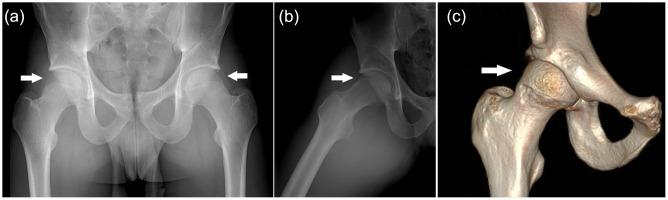

Femoroacetabular impingement (FAI) alters hip mechanics, results in hip pain, and may lead to secondary osteoarthritis (OA) in the maturing athlete. Hip impingement can be caused by osseous abnormalities in the proximal femur or acetabulum. These impingement lesions may cause altered loads within the hip joint, which result in repetitive collision damage or sheer forces to the chondral surfaces and acetabular labrum. These anatomic lesions and resultant abnormal mechanics may lead to early osteoarthritic changes.

股骨髋臼撞击症(FAI)改变髋关节力学,导致髋关节疼痛,并可能导致成熟运动员的继发性骨关节炎(OA)。髋关节撞击可由股骨近端或髋臼的骨性异常引起。这些撞击病变可能导致髋关节内负荷改变,从而导致软骨表面和髋臼盂唇的反复碰撞损伤或剪切力。这些解剖学病变和由此产生的异常力学可能导致早期骨关节炎变化。